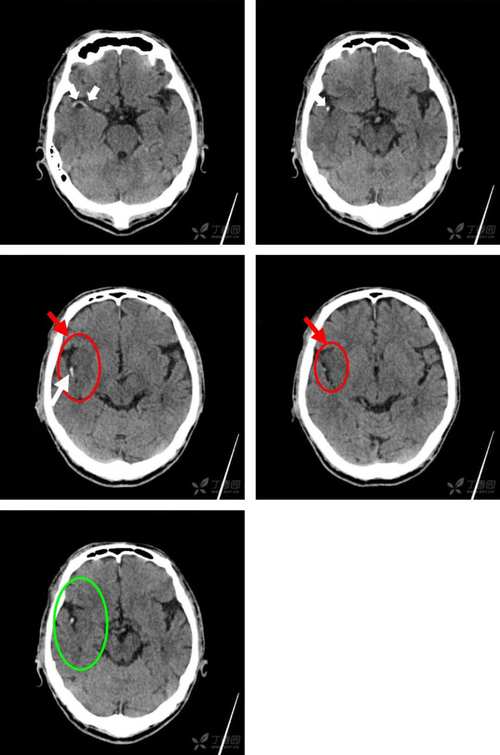

- 明确责任病灶:医生会结合您的临床症状(如偏瘫、失语、口角歪斜等),确定MRI上显示的新发梗死区域是否是导致您当前症状的原因。

- 评估梗死类型和机制:

- 大血管闭塞?:医生可能会安排磁共振血管成像(MRA)或CT血管造影(CTA),查看颅内大血管是否有堵塞或严重狭窄,这是决定是否进行静脉溶栓或机械取栓的关键。

- 小血管病变?:如果梗死灶很小,位于脑深部,可能提示小血管病变(如高血压引起的腔隙性脑梗)。

- 心源性栓塞?:医生会追问您是否有心房颤动(房颤)、心脏瓣膜病等病史,并可能建议做心脏超声(TTE/TEE)等检查,寻找栓子的来源。